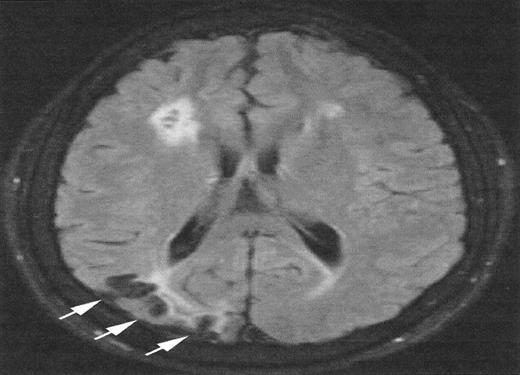

The relationship between SCI and other patterns of brain injury that can be seen in children with SCA is not well defined. In part, this is because SCI can only be identified with surveillance MRI evaluations, which have only recently become routine in some clinical centers. A common finding is cerebral atrophy. This is a non-specific finding that serves as a marker for disease severity in the brain. Another common finding is Moya-Moya, a description that comes from the Japanese for “puff of smoke” because of the angiographic appearance of secondary extensive collateral formation. Figure 2 is a time-of-flight MRI angiogram in a child with SCA and Moya-Moya. The arrows indicate the stenosis/occlusion of the distal internal carotid arteries. The child with SCA and Moya-Moya shown in Figure 3 has an extensive area of cortical infarction corresponding to the distribution of the posterior cerebral artery (arrows) and silent cerebral infarct in the frontal regions.

Magnetic resonance imaging (MRI) from a child with sickle cell anemia (SCA) and Moya-Moya.

The severe hemodynamic compromise associated with the Moya-Moya vasculopathy is associated with overt stroke secondary to a right parietal cortical infarction (white arrows). The signal hyperintensities in the frontal regions correspond to silent cerebral infarctions.